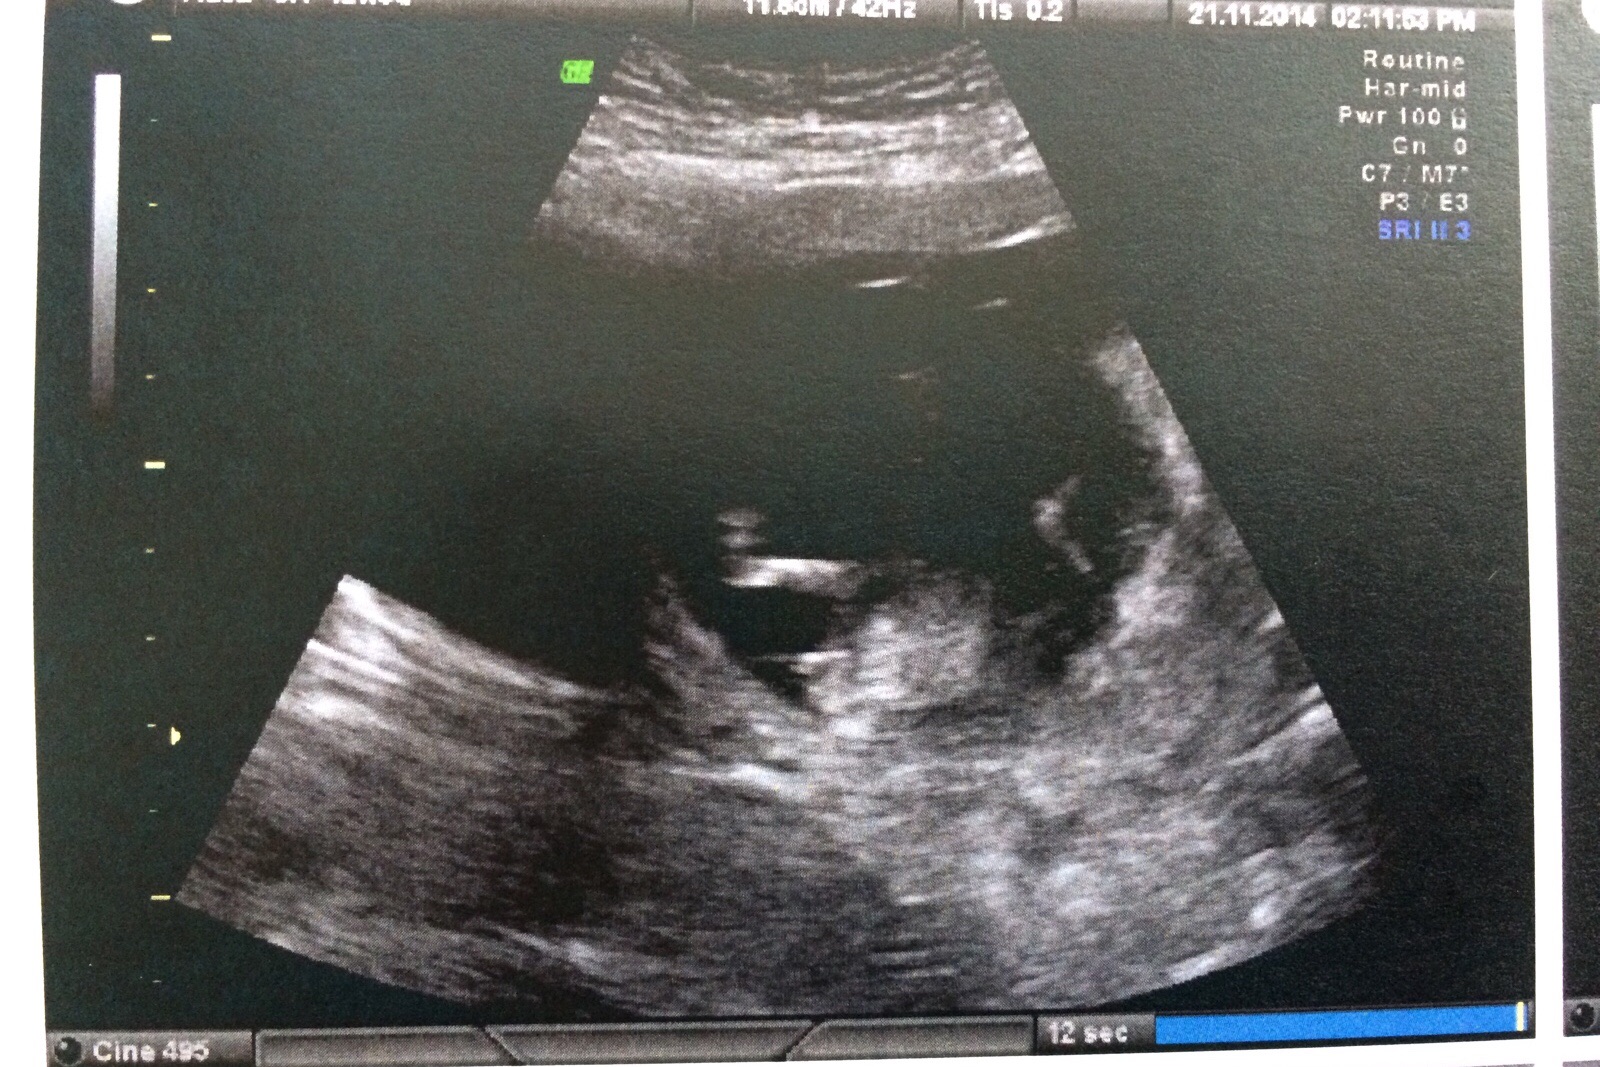

This is my 12 week scan but I am not sure if the nub is visible or how to 'guess' what it is.

Would appreciate your expert opionions. Attachment 22286